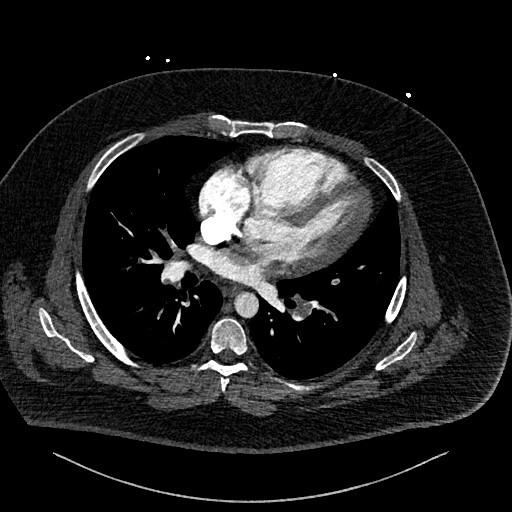

This prompted a re-evaluation of the initial CTPA by a specialist cardiothoracic radiologist. The following figures show selected images from the CTPA. Figure 1 is an axial slice demonstrating the already known bilateral filling defects within branches of the pulmonary arterial system, consistent with PEs (stars).